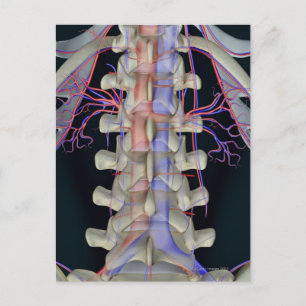

Blodtillförsel av ländkotor vykort

Pris21,00 kr

Blodtillförsel av ländkotor poster

Pris297,00 kr